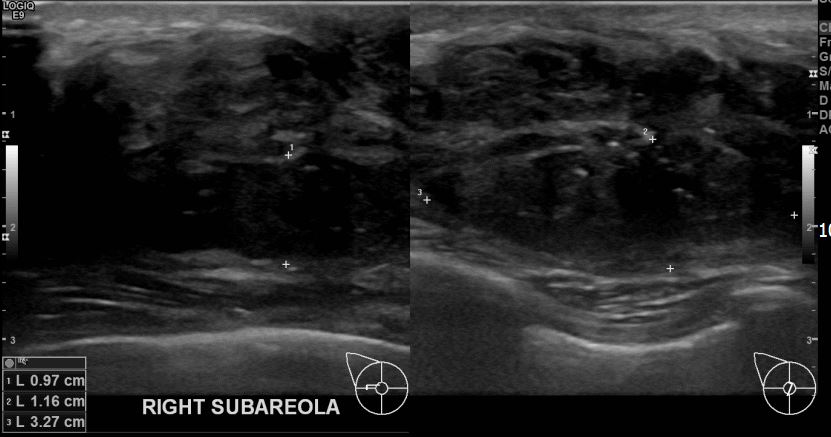

아산유외과개원후 705번째 유방암진단

상기환자 우측유방멍울만져져 내원하신 50대 여성분으로 유방암의심혹 조직검사 시행 후 유방암 진단되었습니다.